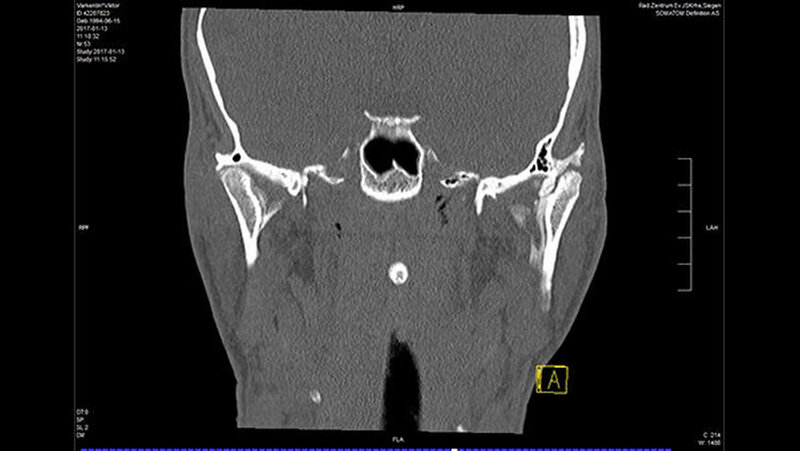

In der Folge entwickelte sich binnen fünf Monaten eine absolute Mundöffnungsbehinderung. Die SKD betrug null Millimeter. Passend zur klinischen Symptomatik zeigten sich radiologisch die Zeichen einer knöchernen Ankylose der Kiefergelenke beidseits Typ III nach Sawhney [1986] (Abbildung 1a-d).